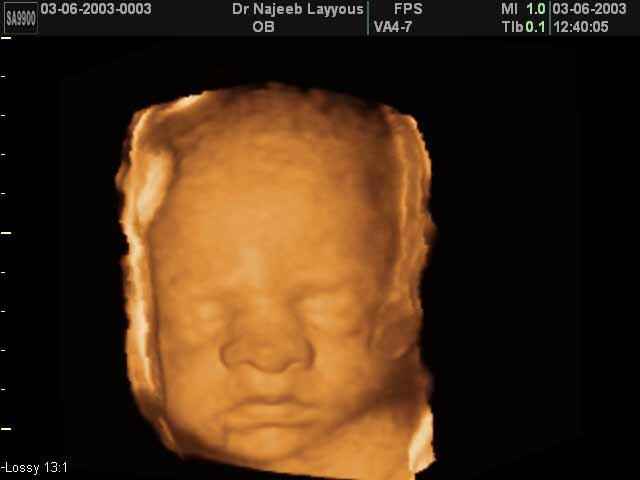

3D Fetal Face Ultrasound Scan Photos